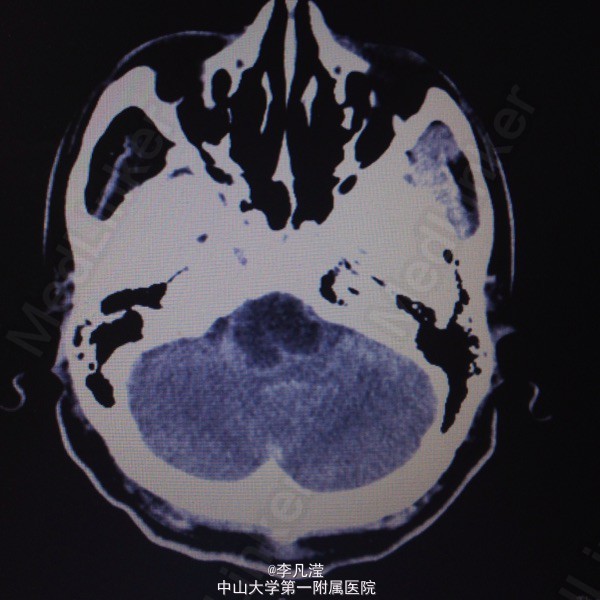

三叉神经鞘瘤一例

右侧中后颅窝底肿块,考虑三叉神经鞘瘤,右侧颞骨岩尖及海绵窦区骨质吸收,右侧麦氏孔扩大,侧脑室及第三脑室轻度积水。

右侧三叉神经鞘瘤